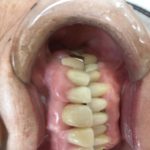

奥歯セラミック

2021年1月31日(日)

皆さまこんにちは!

この患者さまは奥歯をきれいにして堂々と

お口を開けたいとのことでした。

セラミックブリッジ

間違いないきれいさです。

セットし、この患者さまは💕

次のブログへ❤️❤️❤️❤️